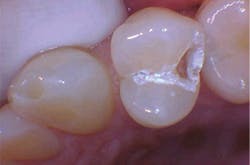

With the help of magnification, we are able to prepare small Class II lesions without sacrificing the marginal ridge, ensuring the longevity of our restoration and maximizing the remaining tooth structure with this minimally invasive approach (figures 3a–3d).

Figures 3a–3d: Minimally invasive Class II preparation with marginal ridge preservation